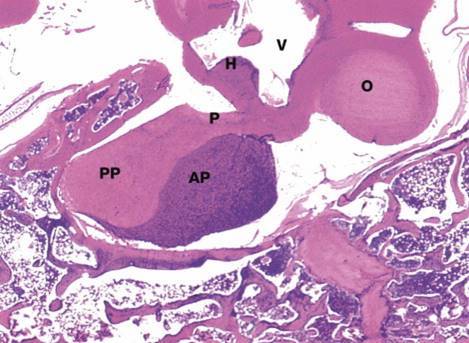

Identify the indicated structures.

AP: anterior pituitary

PP: posterior pituitary

P: pituitary stalk (infundibulum)

H: hypothalamus

V: ventricle

O: optic chiasm